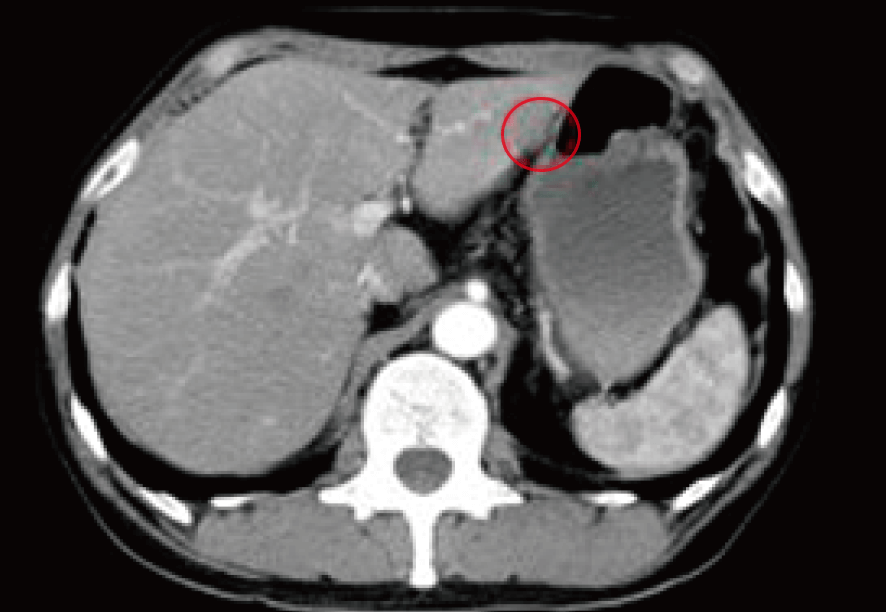

しかも肝臓に複数の転移がんが発見され、これによる臓器障害も尿の出を悪くしていたのだった。

この時点での診断は“大腸がん+遠隔転移(肝臓)”であった。

進行がんの中では最も進行してしまったステージ4である。